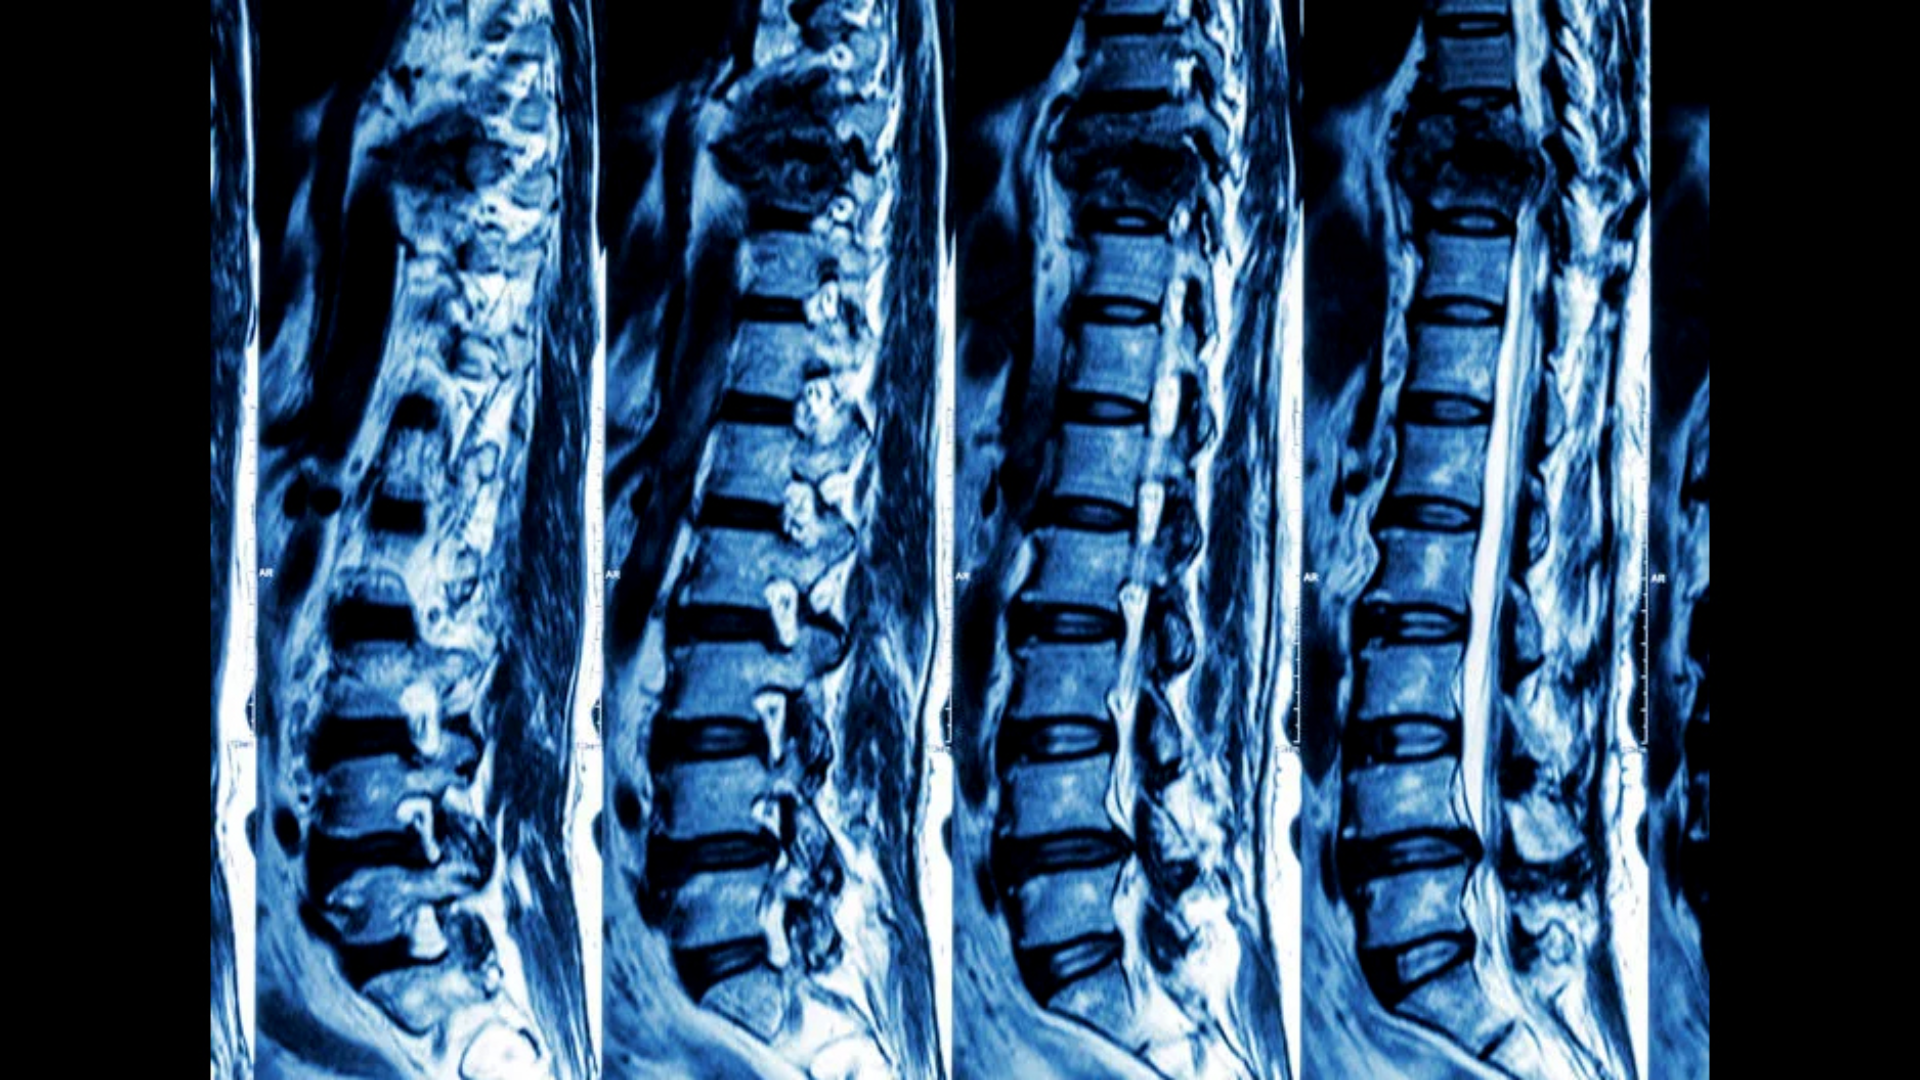

Chụp CT cột sống là kỹ thuật chẩn đoán hình ảnh sử dụng tia X kết hợp với hệ thống máy tính để tạo ra hình ảnh cắt lớp chi tiết của cột sống. Phương pháp này cho phép quan sát rõ cấu trúc xương cột sống theo từng lát cắt mỏng, giúp phát hiện các tổn thương mà X-quang thường khó đánh giá.

CT cột sống có thể khảo sát từng đoạn riêng lẻ như cột sống cổ, cột sống ngực, cột sống thắt lưng hoặc toàn bộ cột sống tùy theo chỉ định lâm sàng. Trong nhiều trường hợp cấp cứu, CT là phương tiện chẩn đoán được ưu tiên nhờ tốc độ nhanh và khả năng phát hiện tổn thương xương chính xác.

CT cột sống phù hợp để đánh giá xương và cấu trúc cứng, đặc biệt trong chấn thương và cấp cứu. MRI cột sống lại ưu thế trong đánh giá mô mềm như đĩa đệm, tủy sống, dây chằng và rễ thần kinh.